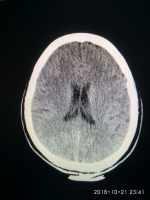

反應遲鈍伴惡心嘔吐一例 關(guān)鍵疾?。?a href="http://m.akellydesign.com/tags/so/嘔吐-4-1.html" target="_blank">嘔吐 現(xiàn)病史【一般資料】男性,78歲,農(nóng)民【主訴】反應遲鈍伴惡心、嘔吐1小時入院【現(xiàn)病史】入院前1小時,晨起后出現(xiàn)反應遲鈍,伴惡心、嘔吐,嘔吐物為胃內(nèi)容物,不含咖啡樣物質(zhì),嘔吐物中含血絲;無頭暈、頭痛,無耳鳴,無意識障礙及大小便失禁,無流涎,無咳嗽、咳痰,腹痛、腹瀉。為求診治,急撥打“120”入院,頭顱CT:左基底節(jié)區(qū)腦腔隙,老年腦。以“1.缺血性腦血管病;2.高血壓2級”收入院。自發(fā)病來,精神較差,食欲較差,睡眠及二便如常?!炯韧贰考韧X梗死2年,有步態(tài)不穩(wěn)后遺癥。無肝炎、結(jié)核、傷寒、瘧疾等傳染病史...

腦便死伴肢體無力大小便失禁一例 關(guān)鍵疾?。?a href="http://m.akellydesign.com/tags/so/腦便死-4-1.html" target="_blank">腦便死高血壓腦梗死后遺癥 現(xiàn)病史【一般資料】女性,58歲,農(nóng)民【主訴】右側(cè)肢體無力1小時入院【現(xiàn)病史】院前1小時,無明顯誘因下出現(xiàn)右側(cè)肢體無力,呈持續(xù)性,不能自行站立及行走伴言語不利,無頭暈,頭痛,無惡心、嘔吐,無意識障礙及大小便失禁,無流涎無嗽,咳,無胸悶、氣短,無腹痛,為求診治,急來我院就診,頭顱CT;左深及頂葉陳舊性梗塞,右基底節(jié)區(qū)腦腔障。以“腦梗死”收入院。自發(fā)病來,精神較差,食欲減迅,睡眠及二便如常?!炯韧贰考茸「哐獕翰∈?8年,口服硝苯地平,6年前患腦梗死,留有言語不利后遺癥;無肝炎、結(jié)核、傷寒、瘧疾等傳染病...

高血壓急癥伴頭痛伴間斷惡心一例 關(guān)鍵疾病:高血壓3級(極高危),高血壓性腦病 現(xiàn)病史【一般資料】 女性,45歲,職員 【主訴】 發(fā)現(xiàn)高血壓3個月,頭痛伴間斷惡心、嘔吐1天入院。 【現(xiàn)病史】于入院前3個月,無明顯誘因出現(xiàn)頭痛不適,無發(fā)熱,不伴惡心、嘔吐,當時測血壓“160/120mmhg”,口服藥物(具體不詳)治療,病情好轉(zhuǎn),測血壓正常后,停用藥物治療,3個月來,患者未監(jiān)測血壓,一般情況可。1天前,患者再次出現(xiàn)頭痛,頭痛呈彌漫性全頭痛,伴間斷惡心、嘔吐,吐物為胃內(nèi)容物,非噴射狀,無膽汁及血絲,當?shù)販y血壓“160/120mmhg”,無明顯頭暈,神志清,精神差,雙上肢麻木不適,無...

腦梗塞致雙下肢活動不利伴高血壓病一例 關(guān)鍵疾?。?a href="http://m.akellydesign.com/tags/so/腦梗塞-4-1.html" target="_blank">腦梗塞高血壓 現(xiàn)病史【一般資料】男性,71歲,農(nóng)民【主訴】雙下肢活動不利1年余,加重2天入院?!粳F(xiàn)病史】于入院前1年,無明顯誘因出現(xiàn)雙下肢活動不利,不能行走,當時無頭痛、頭暈,無惡心、嘔吐,無口角歪斜、流涎,無飲水嗆咳,無胸悶、胸痛,無腹痛、腹瀉,就診于當?shù)卦\所,診斷“腦梗塞”予以治療后病情好轉(zhuǎn),但反應較前遲鈍,1年來,患者病情相對平穩(wěn),近2天來,患者病情加重,故為進一步診治而來我院,頭顱CT示:腦動脈硬化性白質(zhì)腦病。以“腦梗塞”收入院。自發(fā)病以來,患者神志清,精神可,食欲及睡眠可,大小便如常?!炯韧贰扛哐獕?..

無明顯誘因出現(xiàn)言語不利,口齒不清一例 關(guān)鍵疾?。?a href="http://m.akellydesign.com/tags/so/腦梗塞-4-1.html" target="_blank">腦梗塞 現(xiàn)病史【一般資料】男性,69歲,農(nóng)民【主訴】言語不利1天入院【現(xiàn)病史】入院前1天無明顯誘因出現(xiàn)言語不利,口齒不清,無頭痛、頭暈,無耳鳴、視物模糊,無發(fā)熱、大汗,無胸悶、胸痛,當時在家未正規(guī)治療,今日為進一步診治急***就診,門診查頭顱CT示:兩側(cè)基底節(jié)區(qū)腔梗老年腦。以“腦梗塞”收入我科。自發(fā)病以來,精神可,飲食可,睡眠較好,二便正常?!炯韧贰炕颊叻裾J高血壓病史,否認冠心病病史,否認糖尿病病史,無肝炎結(jié)核及其他傳染病病史,無外傷手術(shù)及藥物過敏史?!静轶w】T:36.5℃ ,P:77次/分,R:19次...